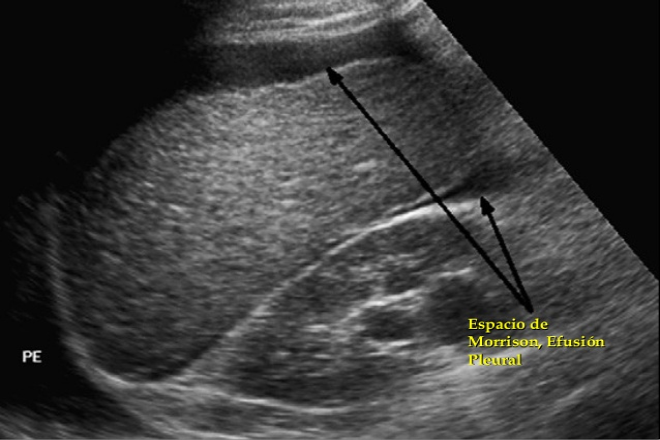

La Ecografía abdominal Enfocada al Ttrauma (FAST) es un protocolo de ecografía abdominal que puede ser realizado por no radiólogos después de un entrenamiento específico y es una competencia básica para todos los alumnos del Reino Unido en medicina de urgencias. Los operadores están entrenados para buscar líquido libre intraabdominal. La ecografía se puede realizar simultáneamente con la reanimación y debe tomar menos de dos minutos. La Ecografía FAST es particularmente útil en pacientes hemodinámicamente inestables, ya que es altamente accesible, rápida de realizar, portátil y no invasiva.

La técnica, sin embargo, tiene limitaciones en los pacientes obesos, es dependiente del operador, y las lesiones intraabdominales pueden pasarse por alto como se evidencia mediante una revisión sistemática.

Una ecografía negativa, por lo tanto, no descarta la lesión y, en estos casos, las imágenes de tomografía computarizada se recomiendan en pacientes hemodinámicamente estables.